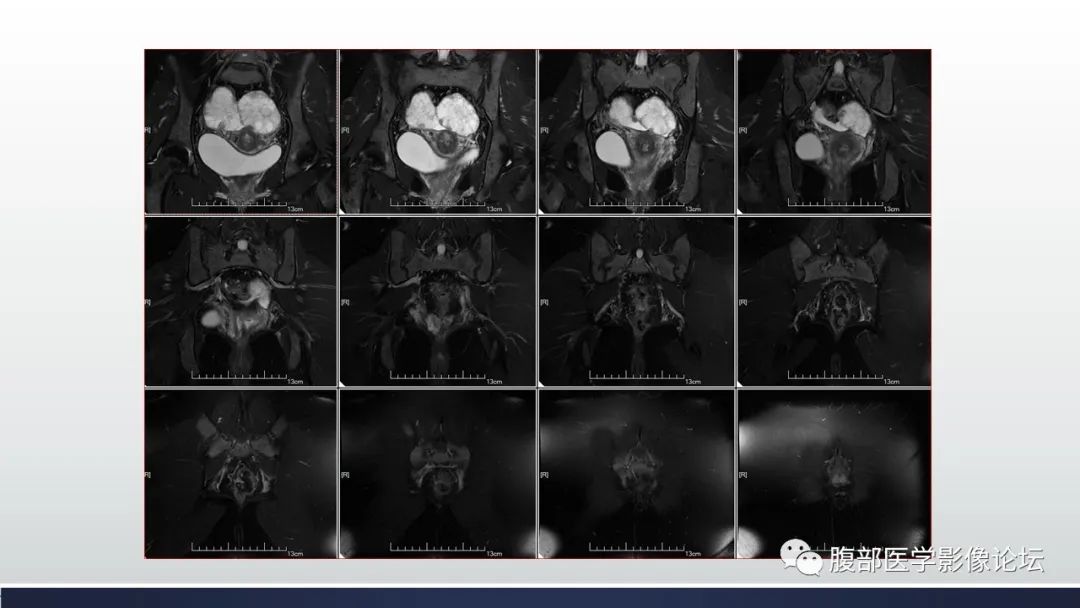

【病例】子宫内膜透明细胞癌1例MR-5

【病例】子宫内膜透明细胞癌1例MR-6